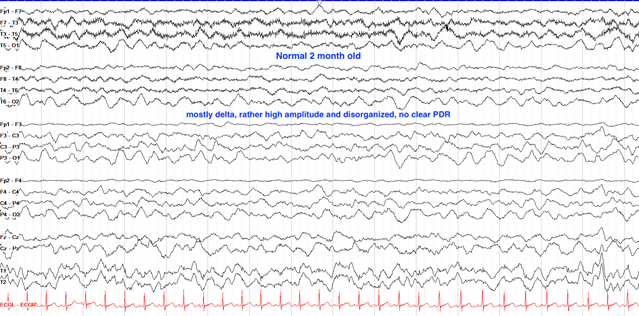

婴儿出生第一年的脑电图特征主要是大量缓慢、高振幅的δ波活动,这些记录应是连续且对称的。在婴儿2至4个月大之前,脑电活动不受睁眼状态影响;而在大约6个月大时,清醒状态下开始出现4至5赫兹的后放电反应。随着婴儿接近一岁,θ波逐渐加入到脑电活动中。困倦状态下,脑电背景依旧非常缓慢和高振幅,特别是在初期,常见1至2赫兹的波动,振幅可达200微伏。到了一岁时,清醒状态下的后放电反应频率增加到约6赫兹。这一系列变化体现了婴儿大脑发育的正常过程。

婴儿期(1-12个月)

1.正常发育模式